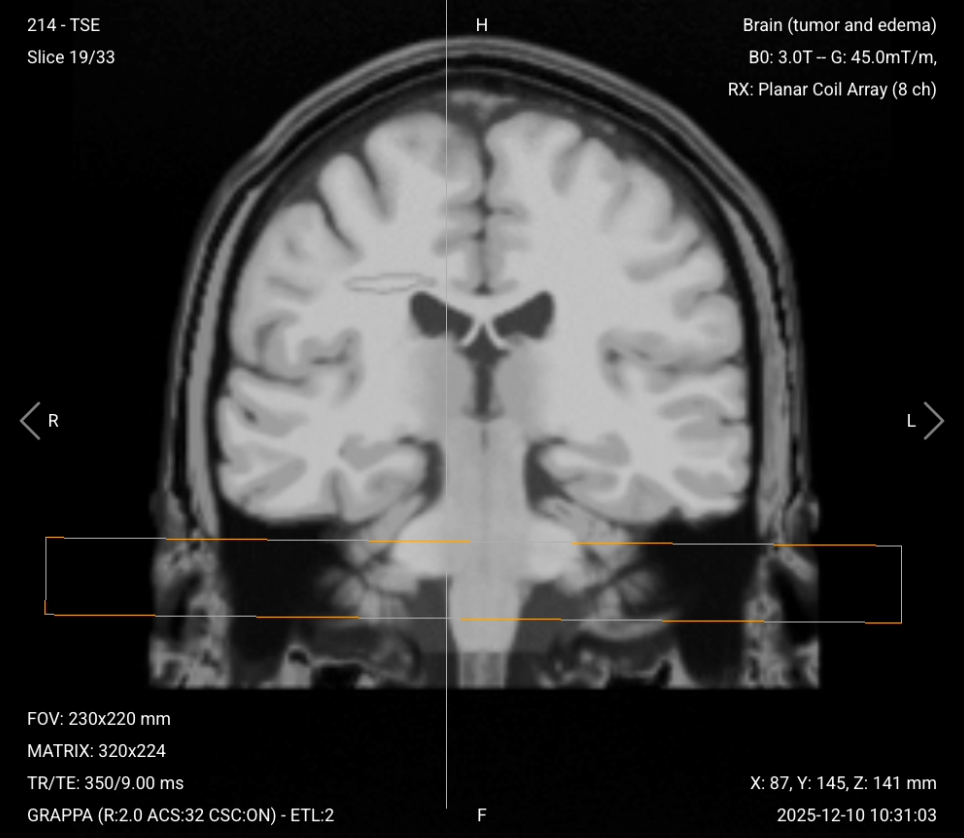

3. Planning Coronal T1 TSE with Fat Suppression (Post-Contrast)

✅ Correct Planning:

Planning Coronal T1 TSE with Fat Suppression (Post-Contrast) – Correct Planning

Planning Instructions:

• Use the post-contrast sagittal T1 3D MP-RAGE for planning.

• Align the slices as follows:

• Sagittal Localizer: Perpendicular to the midsagittal line of the brain.

• Axial Localizer: Ensure slices run from anterior (frontal lobe) to posterior (occipital lobe) without cutting out any anatomy.

• Use appropriate geometry parameters:

• Slice number: Enough to cover from the posterior fossa to the frontal lobe (typically 20-25 slices).

• Slice thickness: 6 mm, medium thickness for good resolution without sacrificing scan time or SNR.

• Slice gap: 1 mm, approximately 20% of slice thickness to provide continuity and avoid cross-talk.

• Set the fold-over direction (phase encoding) to right-left (RL) to minimize wraparound artifacts and allow the smallest field of view.

• This sequence should be acquired at approximately 13-15 minutes post-injection.

Parameters for Post-Contrast Coronal T1 TSE with Fat Suppression:

Parameter Recommended Values Why These Values

Echo Time (TE) 8–12 ms Short TE is required for T1 contrast.

Repetition Time (TR) 350–600 ms Short TR is required for T1 contrast.

Field-of-View (FOV) 230 × 220 mm Optimized for coronal orientation covering brain from anterior to posterior.

Matrix 320 × 224 High matrix provides excellent spatial resolution for detecting small enhancing lesions.

Foldover Direction (Phase) Right-to-Left (RL) Minimizes wraparound artifacts and optimizes FOV for brain shape in coronal view.

Number of Slices 30–35 Enough slices to fully cover from posterior fossa to frontal lobe.

Slice Thickness 4 mm Medium thickness balances resolution with SNR and scan time.

Slice Gap 1 mm Minimal gap provides continuity between slices while avoiding cross-talk.

NEX / Averages 3 Higher averaging improves SNR for detecting subtle enhancement.

Turbo Factor / ETL 3–5 Low turbo factor maintains T1 weighting and avoids T2 contamination.

Bandwidth 244 Hz/px Medium bandwidth balances SNR with chemical shift artifacts.

Refocusing Flip Angle 180° Standard refocusing angle for TSE sequences.

Fold-over Suppression Yes Prevents wrap-around artifacts from posterior structures.

Fat Suppression Spectral Eliminates fat signal to make true contrast enhancement clearly visible. If spectral fat suppression fails at 3 Tesla, use STIR or inversion recovery instead.

Post-Contrast Coronal T1 with Fat Suppression – Assesses Superior-Inferior Extent

Post-contrast coronal T1 with fat suppression provides a frontal perspective of tumor enhancement with fat signal eliminated.

In brain tumor imaging, coronal post-contrast T1 with fat suppression assesses the superior-inferior extent of the tumor and its enhancement. This view is particularly useful for identifying dural involvement, meningeal spread, and skull base invasion. Fat suppression clarifies enhancement along the meninges and skull base where fat might otherwise obscure pathology. This sequence complements the sagittal and axial post-contrast images for complete three-dimensional assessment.

We acquire this sequence in coronal orientation to complete the three orthogonal planes and provide optimal assessment of superior-inferior tumor relationships.

Coronal T1 with Fat Suppression (Post-Contrast) – Correct Image Example:

Coronal T1 with Fat Suppression (Post-Contrast) – Correct Image Example

Things to Look for in Post-Contrast Coronal T1 with Fat Suppression:

• Superior-inferior tumor extent and enhancement

• Dural involvement or meningeal spread along brain surface

• Skull base invasion

• Relationship to cranial nerves and vascular structures